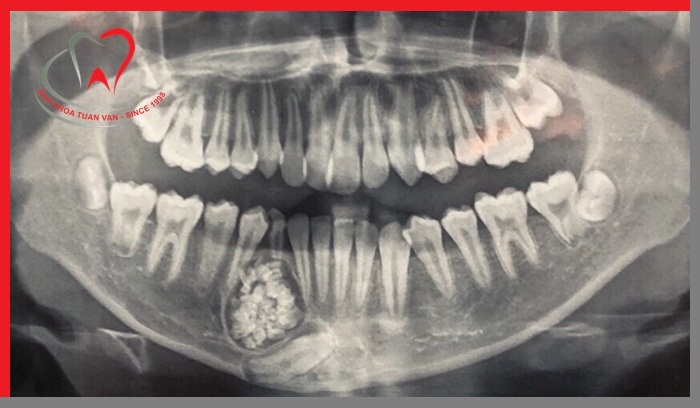

- Trong quá trình điều trị một khối u nào đó ở vùng hàm mặt, những răng nằm trên đường đi của tia xạ trong việc điều trị cũng sẽ được nhổ bỏ.

Khối u trong hàm cần chỉ định nhổ răng

Bước 1: Thăm khám cấu trúc răng cần nhổ và kiểm tra sức khỏe răng miệng

Bác sĩ sẽ tiến hành thăm khám, chụp X - Quang để xác định chiều dài, hình dạng, vị trí và tình trạng xương xung quanh vị trí răng cần nhổ. Từ đó, bác sĩ ước tính mức độ khó của ca tiểu phẫu và hướng nhổ răng hợp lý nhất.

4. Chụp phim khảo sát trước khi nhổ răng

Trước khi thực hiện nhổ răng, các bác sĩ tại Nha khoa Tuấn Vân sẽ tiến hành thăm khám và chỉ định chụp phim X – quang trước. Việc thực hiện chụp phim khảo sát giúp bác sĩ xác định chính xác vị trí, hướng mọc, hình dáng của răng, xác định được hình thể cũng như số chân răng. Qua phim X – quang, bác sĩ sẽ tiên lượng được độ khó dễ của răng và đưa ra phương pháp nhổ răng phù hợp, an toàn với từng trường hợp.